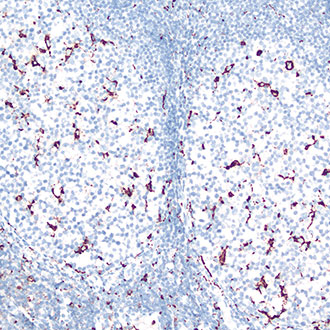

CD68

CD68 -